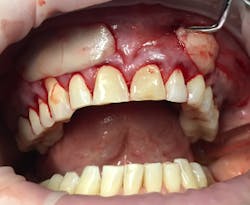

This new biological approach involving blood derivatives A-PRF and I-PRF combined with precision minimally invasive surgery for root coverage demonstrates faster healing without the need of a donor site. The morbidity of GDT is decreased and patient case acceptance is higher compared with traditional grafts. Before-and-after pictures are shown below (figures 15–22).